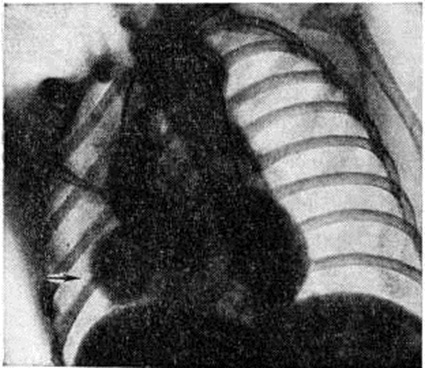

Диагноз. При аортальном стенозе данные векторкардиографии (смотри полный свод знаний) отражают подъём левожелудочкового давления лучше, чем ЭКГ. Только заметное повышение давления (градиент давления на уровне сужения более 60 миллиметров ртутного столба) приводит к появлению на ЭКГ признаков гипертрофии левого желудочка. У новорождённых на ЭКГ могут быть лишь признаки гипертрофии правого желудочка. Характерные клинические, симптомы в сочетании с признаками гипертрофии левого желудочка на ЭКГ указывают на выраженный аортальный стеноз (рисунок 3). При рентгенологическое исследовании у детей тень сердца нормальных размеров или с признаками гипертрофии левого желудочка. При высоком конечно-диастолическом давлении в левом желудочке и левом предсердии отмечаются застойные явления в прикорневых отделах лёгких. Может быть расширена восходящая часть аорты (постстенотическая дилатация). У детей с выраженным стенозом рентгенологически определяется аортальная конфигурация сердца (рисунок 4) и усиленный легочно-сосудистый рисунок. При ретроградной катетеризации сердца катетер проводят через место сужения в полость левого желудочка, измеряют градиент давления, выявляют место сужения и возможные сопутствующие пороки. У новорождённых и грудных детей катетеризация сердца может быть заменена эхокардиографическим исследованием (смотри полный свод знаний: Эхокардиография). У больных с асимметричной перегородочной гипертрофией во время систолы происходит смыкание передней створки левого предсердножелудочкового (митрального) клапана с гипертрофированным миокардом. Сужение может сопровождаться большим градиентом давления. При нагрузках, приёме сердечных гликозидов или инотропных средств и нитроглицерина градиент давления возрастает, но снижается при использовании р-адреноблокаторов (анаприлина, обзидана, индерала). Во время систолы, следующей после экстрасистолы, артериальное давление уменьшается, в то время как при других видах аортальногостеноза оно возрастает. При массивной мышечной гипертрофии возникает обструкция выходного отдела левого желудочка, нарушается функция митрального клапана. Признаки заболевания аналогичны таковым при других видах аортального стеноза, однако на ЭКГ всегда регистрируют выраженную гипертрофию левого желудочка, удлинение интервала Q — Г, изменения S — Г, зубцов Т и Q. Диагноз может быть установлен достаточно точно с помощью эхокардиографии. Во время катетеризации сердца на киноангиокардиограмме (смотри полный свод знаний: Ангиокардиография) в боковой проекции видно сужение полости левого желудочка в его выходной части. Детей с сердечной недостаточностью оперируют по жизненным показаниям. Так называемый плановые операции при аортальном стенозе выполняют, если в покое градиент давления на уровне сужения выше 60 миллиметров ртутного столба. Аортальную вальвулотомию производят либо по закрытой методике (через верхушку сердца в аорту последовательно проводят вальвулотом и дилататор), либо на «открытом» сердце в условиях умеренной гипотермии (общей или краниоцеребральной) при пережатых полых венах. Доступ — через стенку аорты. В течение 3—5 минут рассекают клапан по комиссурам. Безопаснее устранять порок в условиях искусственного кровообращения. Наибольшие трудности возникают при коррекции надклапанного сужения с гипоплазией аорты, что требует вшивания заплаты в стенку аорты, иногда с протезированием клапанов сердца (смотри полный свод знаний), и асимметричной гипертрофии миокарда. Иссечение мышечных масс может быть выполнено из аортального доступа, который иногда приходится дополнять рассечением стенки левого желудочка. Существуют методики, предусматривающие иссечение миокарда со стороны правого желудочка. К более радикальным операциям относится иссечение миокарда через левое предсердно-желудочковое отверстие с последующим протезированием митрального клапана. Ок. 10% неоперированных детей раннего возраста имеют явные признаки левожелудочковой недостаточности. В течение первого года жизни (особенно первого месяца) большая их часть погибает. У выживших со средней степенью сужения клинические, признаки Пороки сердца врождённые с возрастом нарастают. Страдающие тяжёлой формой стеноза в 1—7% случаев умирают внезапно. В 20% случаев при стенозе развивается регургитация. При асимметричной гипертрофии перегородки сердца продолжительность жизни ограничена 40—50 годами. Результаты оперативного лечения во многом определяются исходной степенью тяжести стеноза, его морфологией, состоянием миокарда левого желудочка, радикальностью оперативного вмешательства и отсутствием послеоперационной недостаточности клапана. Операционная летальность не превышает 10%. Через 10 лет около 25% оперированных нуждается в повторном вмешательстве для ликвидации рестеноза или регургитации. Во время повторных операций, как правило, производят протезирование клапана. У остальных отдалённые результаты хорошие и удовлетворительные: большая часть из них может считаться практически здоровыми. Аортолёгочный свищ — врождённое соустье между восходящей частью аорты и лёгочным стволом — относится к редким аномалиям (0,3% всех врождённых пороков «сердца.). На 8-й неделе у эмбриона формируется спиральная перегородка, которая при нормальном развитии делит общий артериальный ствол на два продольных канала (аорту и лёгочный ствол) и срастается в области их фиброзных колец с межжелудочковой перегородкой. Нарушения механизма образования перегородки приводят к появлению патологический отверстия между двумя магистральными сосудами. В большинстве случаев дефект располагается на 1—5 миллиметров выше фиброзного кольца устья аорты. Реже отверстие достигает клапанов аорты и лишь иногда располагается в дистальной х/3 восходящей части аорты. Размеры соустья варьируют широко — от 2 до 30 миллиметров. Отсутствие межсосудистой перегородки от клапанов аорты до дистального отдела восходящей части аорты может рассматриваться как общий артериальный ствол. Характер гемодинамических нарушений при аортолёгочном свище во многом сходен с расстройствами кровообращения при открытом артериальном протоке. Однако вследствие близости патологический отверстия к устью аорты (отверстие аорты) осложнения развиваются быстрее, в частности лёгочная гипертензия. Клиническая картина определяется размерами аортолёгочного свища и состоянием сосудов лёгких. При небольших размерах свища (менее 5 миллиметров) течение порока аналогично таковому при артериальном протоке. Однако эпицентр систолодиастолического шума при этом пороке располагается ближе к средней линии во втором межреберье у грудины. При средних размерах свища (6—10 миллиметров) клинические, проявления более тяжёлые, чем при артериальном протоке такого же диаметра. Отмечается бледность, ребёнок отстаёт в физическом развитии, у него легко возникает одышка, даже при небольших физических нагрузках; характерны слабость, повышенная утомляемость. Большой свищ (более 10 миллиметров) сопровождается высокой лёгочной гипертензией, поэтому возникновение цианоза, приступов одышки, нарушений ритма (вначале лишь при нагрузках) свидетельствует о выравнивании давления в аорте и лёгочном стволе и двустороннем шунтировании крови. В этот период может проявиться сердечная недостаточность. До развития лёгочной гипертензии (при малых и средних размерах свища) клинические, признаки порока во многом совпадают с проявлениями артериального протока (систолодиастолический шум, дрожание над сердцем и другие). При развитии лёгочной гипертензии вначале исчезает диастолический шум, а затем ослабевает и систолический. На ЭКГ в зависимости от степени нарушений гемодинамики определяются признаки перегрузки левого, обоих или преимущественно правого желудочка, нарушения сердечного ритма (пароксизмальная тахикардия, экстрасистолия). При рентгенологическое исследовании — изменения размеров сердца и сосудов лёгких взаимосвязаны с величиной и направлением сброса крови. При большом артериовенозном сбросе увеличены основание и левые отделы сердца, усилен лёгочный рисунок, выбухает дуга лёгочного ствола; при сбалансированном шунте наблюдается гипертрофия обоих желудочков, обеднение сосудистого рисунка по периферии лёгких. Катетеризация и контрастирование сердца являются основными методами распознавания порока и установления степени нарушений гемодинамики. Катетер, проведённый из правого желудочка в лёгочный ствол, может попасть через свищ в аорту. В зависимости от величины давления в аорте и лёгочном стволе контрастирование одной из них может дать полное представление о локализации, размерах, направлении и объёме шунта. Для этой цели производят аортографию (смотри полный свод знаний) в прямой и правой косой позиции (с помощью катетера, проведённого ретроградно до клапана аорты). Величина сброса крови может быть установлена также исследованием её на насыщение кислородом в различных участках правых отделов сердца и лёгочном стволе красочными, платиноводородными и термодилюционными пробами. Порок следует дифференцировать с открытым артериальным протоком (смотри полный свод знаний), дефектом межжелудочковой перегородки, стенозом лёгочной артерии, стенозом устья аорты, недостаточностью митрального клапана, разрывом аневризмы синуса Вальсальвы, аневризмами коронарных сосудов, артериовенозными аневризмам левой внутригрудной, межрёберных артерий или перикардиальных сосудов. Лечение оперативное, за исключением больных с выраженной лёгочной гипертензией и преобладающим венозно-артериальным сбросом крови (им показано ограничение в физических нагрузках и терапия сердечной недостаточности). Для закрытия свища существует несколько способов. Свищ, расположенный выше аорты и клапанов лёгочного ствола, перевязывают несколькими лигатурами. Если свищ прилегает к клапану аорты, то его можно ушить со стороны лёгочного ствола (рисунок 5) в условиях умеренной гипотермии с выключением сердца из кровообращения. В большинстве же случаев операция при аортолёгочном свище проводится в условиях искусственного кровообращения. В зависимости от размеров отверстия и продолжительности операции применяется один из видов защиты миокарда (холодовая или медикаментозная кардиоплегия, коронарная перфузия и тому подобное). При дистально пережатых сосудах производят либо ушивание свища, либо вшивание заплаты (что предпочтительно) со стороны аорты или лёгочного ствола. Неоперированные больные с лёгочной гипертензией обычно погибают в детском возрасте. Летальность после операций у больных без выраженной лёгочной гипертензии не превышает 5%, у больных с лёгочной гипертензией более 50%. Результаты в отдалённые сроки после операции в подавляющем большинстве случаев благоприятные. Артериальный проток соединяет аорту с лёгочным стволом. Необходимый в период эмбрионального развития для нормального кровообращения, после рождения ребёнка он облитерируется. Если облитерация не наступает, развиваются нарушения гемодинамики, сброс крови из аорты в лёгочный ствол. Лечение оперативное (смотри полный свод знаний: Артериальный проток). Атрезия лёгочного ствола в сочетании с дефектом межжелудочковой перегородки представляет собой одну из форм тетрады Фалло. Обычно наблюдается гипоплазия правого желудочка (I тип); возможно сочетание нормального или даже расширенного правого желудочка с несостоятельностью трёхстворчатого клапана (II тип). Клапан лёгочного ствола маленький, заращён. Дистальнее его ствол сосуда сохранен. Центральный кровоток осуществляется через дефект перегородки в левые отделы сердца и аорту, далее через артериальный проток в сосуды лёгких. Артериальный проток обычно узкий. Степень цианоза зависит от величины сброса крови через артериальный проток. Цианоз заметен с момента рождения, усиливается с развитием сердечной недостаточности; наблюдаются приступы гипоксии, ацидоз. На ЭКГ отмечаются признаки преобладания левого желудочка, особенно при I типе порока. Рентгенологические исследование выявляет увеличение размеров сердца, лёгочно-сосудистый рисунок ослаблен. При контрастировании сердца виден правый желудочек с выходным отделом в виде слепого мешка и регургитацией в предсердие. Этот порок нужно дифференцировать с трикуспидальной атрезией, тетрадой Фалло, стенозом лёгочного ствола, транспозицией крупных сосудов со стенозом лёгочного ствола. Лечение оперативное. Если правый желудочек недоразвит, то целесообразно наложить межсосудистый анастомоз; если он развит нормально, то производят лёгочную вальвулотомию. В некоторых случаях между правым желудочком и лёгочным стволом вшивают кондуит (консервированный в глутаровом альдегиде биологический трансплантат клапана сердца, вшитый в сосудистый протез). Послеоперационная летальность у новорождённых с гипоплазированным правым желудочком высокая (до 80%). Без операции практически все дети погибают в течение первого года жизни. Атрезия устья аорты сочетается с гипоплазией восходящей части аорты, гипоплазией или атрезией левого желудочка и атрезией или выраженным стенозом митрального клапана. Устья коронарных артерий, как правило, располагаются в луковице аорты. Для поддержания жизни необходимы артериальный проток и дефект межпредсердной перегородки (открытое овальное окно). Кровообращение при этом происходит следующим образом: венозная кровь большого и малого круга кровообращения смешивается в предсердии, поступает в правый желудочек, лёгочный ствол и через артериальный проток в аорту. Аортальная атрезия и другие варианты гипоплазии левых отделов сердца являются самой частой причиной смерти новорождённых с Пороки сердца врождённые Хотя при рождении ребёнок может выглядеть нормально, вскоре выявляется сердечная недостаточность с дилатацией правого желудочка, падением АД и цианозом. Данные физикального, электрокардиографического и рентгенологическое исследований далеко не всегда позволяют правильно распознать порок. Только эхокардиография, катетеризация сердца и киноангиокардиография дают возможность поставить окончательный диагноз и оценить гемодинамические нарушения. Порок считается неизлечимым, оперативное вмешательство не проводится. Большая часть новорождённых с этой патологией погибает в течение нескольких дней после рождения. Атриовентрикулярный канал (неполная форма) представляет собой сочетание первичного дефекта межпредсердной перегородки с расщеплением створки митрального или трёхстворчатого клапана или створок обоих клапанов. Первичный дефект межпредсердной перегородки всегда большой, имеет полулунную форму, сверху отграничен межпредсердной перегородкой, снизу фиброзным кольцом клапанов. Передняя створка митрального клапана расщеплена обычно в середине общей части фиброзного кольца клапана. Аналогично может быть изменена и перегородочная створка трёхстворчатого клапана.. Нарушения гемодинамики аналогичны таковым при первичном дефекте межпредсердной перегородки. Расщепление створки клапана приводит к регургитации крови из желудочка (или обоих желудочков) в оба предсердия; степень регургитации может быть различной. Для детей в возрасте до 3 лет при этом пороке характерна сердечная недостаточность, которая сопровождается одышкой, низкой толерантностью к физическим нагрузкам, резким отставанием в развитии ребёнка. У взрослых, как правило, наблюдаются хронический недостаточность кровообращения, приступы пароксизмальной тахикардии, присоединяется инфекционные эндокардит. Основные физикальные признаки порока: бледность кожи, «сердечный горб», интенсивный систолический шум над верхушкой сердца, расщепленный 11 тон над лёгочным стволом. На ЭКГ выявляются неполная блокада правой ножки пучка Гиса, отклонение электрической оси влево при наличии диастолической перегрузки правого желудочка; на ФКГ — интенсивный систолический шум над верхушкой сердца, расщепление II тона с усилением лёгочного компонента. Рентгенологически отмечается увеличение обоих желудочков, нередко кардиомегалия. При катетеризации сердца обнаруживают низкий дефект межпредсердной перегородки и регургитацию из желудочка при заполнении его контрастным веществом. Лечение — оперативное: из правосторонней торакотомии (смотри полный свод знаний) или срединной стернотомии (смотри полный свод знаний: Медиастинотомия) в условиях искусственного кровообращения расщепленную створку клапана соединяют отдельными П-образными швами, стремясь не сузить клапан. Дефект межпредсердной перегородки закрывают заплатой.